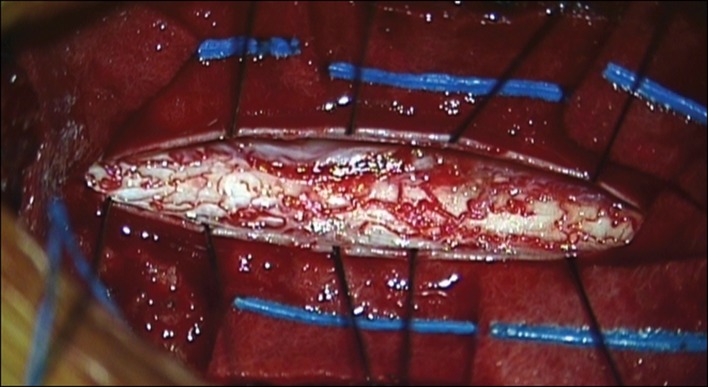

Fig. 2.

a Yellowish cystic mass was noted in the intradural extramedullary space. b Under microscopic magnification, fine arachnoid dissection was performed and the cystic mass was totally removed en-bloc manner. c The cystic mass was 0.5 × 0.5 × 4 cm

Fig. 3.

During and after the dissection, no definite vascular or anatomical abnormal findings of the spinal cord were noted. Only minimal arachnoid thickening was noted around the cystic mass. The remnant of thickened arachnoid was dissected off of the posterior aspect of the cord and was removed